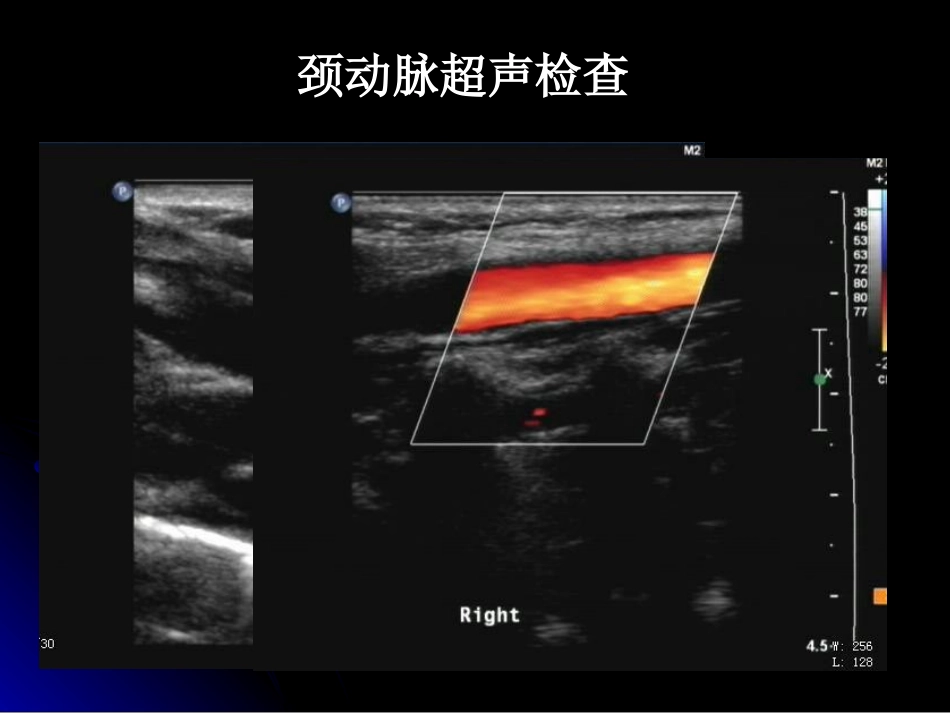

颈、椎动脉超声检查研究生:范春芝2011-8-4颈内动脉:供应大脑椎动脉:供应大脑颈外动脉:供应颅外颜面部组织颈动脉超声检查颈外动脉颈内动脉颈内动脉与颈外动脉的鉴别:解剖位置颈内动脉颈外动脉后外侧前内侧内径较大较小有无分支有无多普勒频谱特征高阻低阻颞浅动脉敲击试验波形锯齿样震荡无颈外动脉颈内动脉颈动脉粥样硬化斑块的超声评价1.低回声斑块含有大量脂类物质2.等回声斑块以胶原蛋白为主要成分3.强回声斑块斑块钙化,后方伴声影颈动脉狭窄的超声诊断1.狭窄前ICA重度狭窄或闭塞,CCA频谱与ECA相似,呈高阻特点,流速降低。2.狭窄处血流速度增快。3.狭窄即后段血流紊乱,呈湍流;频谱表现为频带增宽、双相血流、流速减低。颈内动脉中度狭窄颈总动脉中段重度狭窄颈内动脉狭窄程度的判断:狭窄程度轻度(<50%)中度(50%~69%)重度(≥70%)PSVICAPSVICA/PSVCCA<125cm/s125~230cm/s>230cm/s<2.02.0~4.0>4.0椎动脉超声检查第一部分:近段/椎前段(从锁骨下动脉发出到进入第六颈椎横突孔部分)大多数有血流动力学意义的病变出现在椎动脉起始部检查重点右侧椎动脉椎间段内径3.3mm,椎间段流速38cm/s,右侧椎动脉起始段可见等回声斑块,厚约2.6mm,累及长度约13.6mm,CDFI示其内可见细线状血流信号,该处血流加速,流速约252cm/s,提示该处管腔狭窄,直径狭窄率大于50%。诊断:结论:右侧椎动脉起始部重度狭窄椎动脉起始端狭窄的判断:1.正常呈低阻频谱,PSV<100cm/s2.直径狭窄率接近50%局部PSV>125cm/s,伴有狭窄即后段湍流除外血管走行弯曲导致3.直径狭窄率大于50%局部PSV>150cm/s,伴有狭窄即后段湍流第二部分:中段/横突段(从第六至第二颈椎横突孔部分)此段椎动脉弯曲小,很少受动脉粥样硬化疾病的侵犯。1.椎间段内径(不小于2mm)2.椎间段流速(不小于30cm/s)如果起始部有狭窄,椎间段流速会减低第三部分:远段/寰椎段从第二颈椎出口至基底动脉起始端应用经颅多普勒技术检查。